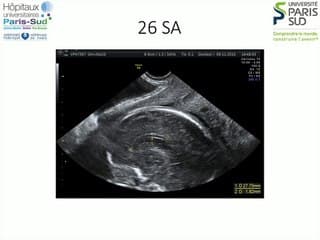

Le Dr Norbert Winer présente une étude multicentrique rétrospective et observationnelle en maternité de niveau 3 sur les grossesses gémellaires mono-choriales mono-amniotiques.Les grossesses gémellaires MCMA sont rares: entre 30 et 50 par an en France. Il n'y a pas de recommandations mais que des suivis de cohortes.L'étude court sur une période de 1998 à 2009. A partir de 12 SA, une fois établi de façon certaine le diagnostic échographique.Les données sont recueillies à partir d'un questionnaire standardisé.Il fallait aussi une anapath du placenta ou au moins une analyse macroscopique de ce placenta.133 femmes ont été inclues. 106 ont été retenues. - la mortalité foetale est aux environs de 25% (ce qui confirme le haut risque de ces grossesses)- les anomalies funiculaires sont signalées dans 25% des cas (seulement) par les échographistes- 33 SA est l'âge moyen de naissance- il y a eu 25% d'accouchement par voie basse.- la mortalité périnatale est aux environs de 15%Le taux de 25% d'anomalies funiculaires dans l'étude est une surprise par rapport à ce qui est relayé habituellementUn consensus existe sur un terme de naissance vers 34 SA (entre 34 SA et 36 SA dit le CNGOF).L'accouchement par césarienne semble être un dogme. Bien qu'il n'existe pas de contrindication formelle à la voie basse.Dans le cas où une voie basse est envisagée, elle doit être discutée en équipe et avec les parents.Le risque étant les accidents ischémiques en per partum.En conclusion:Ce sont des grossesses rares et à haut risque avec une mortalité non négligeable. Le diagnostic échographique est fondamental aussi pour l'analyse des anomalies funiculairesIl faut donc poursuivre le recueil des données.